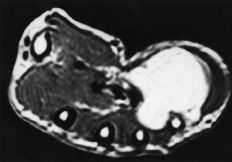

Había 55 tumores derivados de los vasos, de los que 34 eran hemangiomas (20 cavernosos, nueve venosos, tres endoteliales y dos capilares), 12 tumores glómicos, seis leiomiomas, dos fístulas arteriovenosas y un linfangioma. Treinta y siete eran mujeres y 18 hombres, siendo la edad media de 45 ± 15 años (máximo: 73 y mínimo: 8 años). La distribución por edades de los diferentes subtipos histológicos fue extremadamente dispersa. La localización más frecuente fueron los dedos (31 casos), seguido de la palma y eminencias (14 casos) y muñeca y dorso de la mano (5 casos de cada localización). Diez de los tumores glómicos afectaban a mujeres y siete de ellos eran de localización subungueal (Fig. 2).

Los tumores glómicos tienen una localización pulpar, y más concretamente subungueal.2,6,20,22,24-27,34,38,39 En esta serie hubo nueve casos de localización pulpar, de los cuales siete fueron subungueales. Sin embargo, cabe la posibilidad de TPB subungueales que no son tumores glómicos, como un hidroadenoma nodular no incluido en la serie por haber sido tratado fuera de los períodos de estudio. El tumor glómico es una tumoración procedente de la proliferación del glomus mioarterial, anastomosis arterio-venosa con un lecho capilar intermedio que no está presente al nacimiento y se desarrolla en los primeros años de la vida. Las estructuras vasculares están envueltas por numerosas fibras musculares y nerviosas, tanto mielínicas como amielínicas. El cuerpo glómico está rodeado por una cápsula fibrosa. La función principal del glomus es la regulación de la temperatura corporal y la tensión arterial mediante la apertura y cierre de sus anastomosis. Los tumores glómicos se diagnostican cuando su tamaño es superior a 1 mm. La etiología se supone traumática, aunque no está demostrado. Clínicamente se caracterizan por dolor intenso a la presión local, intolerancia al frío, y deformidad, reblandecimiento y decoloración subungueales. En la radiografía convencional, y característicamente en la de alta definición, puede apreciarse una erosión subungueal en los casos de esta localización (Fig. 2).1,2,6,17,24,25,38,39

Figura 2. Tumor glómico subungual. A y B: Rx PA y lateral del extremo del dedo afecto. Obsérvese la erosión ósea (flechas).